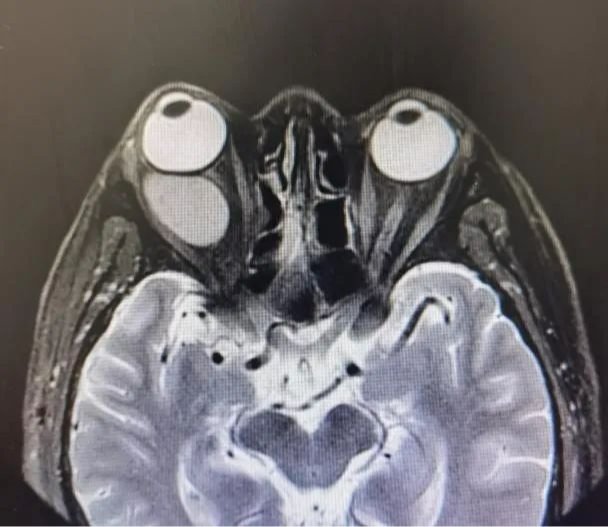

实力雷火电竞 | 高难度“拆弹”!雷火电竞 眼科成功摘除眼眶巨大血管瘤

眼眶内的血管瘤就像一枚潜伏着随时会夺走人视力的“定时炸弹”,而眼科医生就像“拆弹专家”,需要承担极大的风险在复杂的神经血管中小心谨慎地将“炸弹”移除。